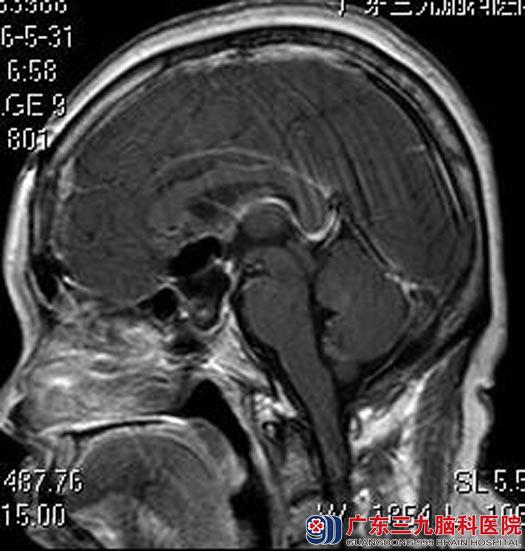

术后,陈女士的双眼视力较前好转,无尿崩、离子紊乱等术后并发症,生活恢复自理,康复出院。

▲术后MR